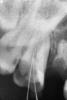

Dandan Опубликовано 7 июня, 2011 Поделиться Опубликовано 7 июня, 2011 (изменено) Здравствуйте, уважаемые коллеги! Нужен ваш совет. Ситуация следующая: зуб № 16. 2 канала, нет намека на 3-й. с небным никаких проблем, щечный непроходимый, плюс ко всему фуркация подвижна. камеру вскрывала я, не было риска перфорации, сразу вскрылись 2 канала. рентген аппарат у меня не очень, так что снимки некачественные. я первый год как работаю, не сталкивалась с такой ситуацией. не могу разобраться в зубе, и не знаю что с ним делать.оставила метапасту в зоне фуркации, у пациента жалоб нет. посоветуйте, как быть... sumare2.bmp Изменено 7 июня, 2011 пользователем Dandan Ссылка на комментарий

Orinoko Опубликовано 7 июня, 2011 Поделиться Опубликовано 7 июня, 2011 Сделайти снимок с файлами на всю длину,а то так ничего непонятно.И ищите 3 канал тогда или совсем рядом с тем щечным ,что вы наши.Или иногда они могут быть по одной линии-так что между ними Ссылка на комментарий